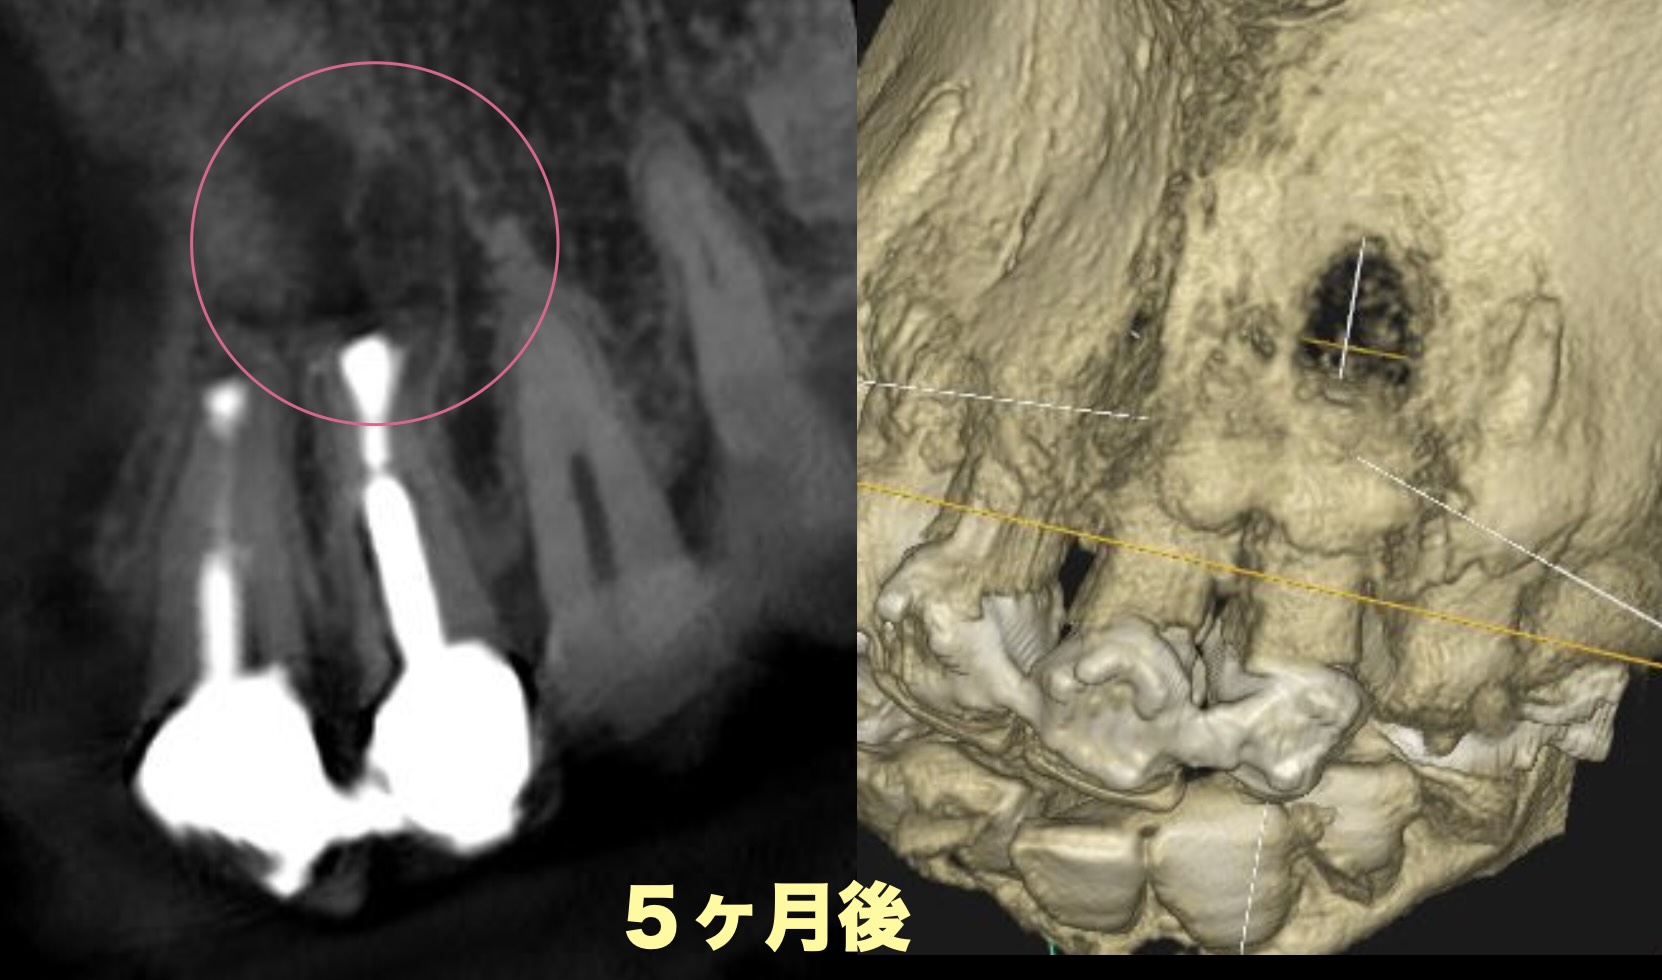

治療後

5ヶ月で、溶けていた骨はしっかり回復してきています。

抜歯と診断された歯でも、ここまで回復することがあります。

現時点で経過は良好で、この歯は保存できる可能性が高い状態です。